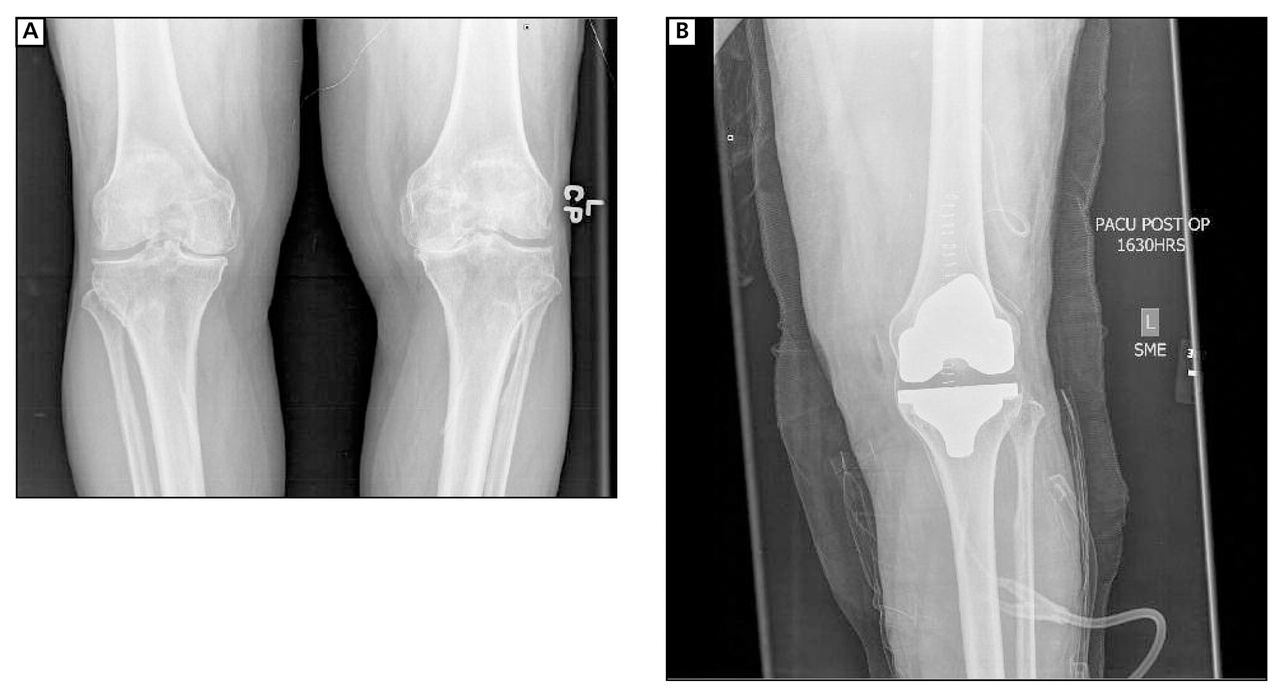

End-stage degenerative knee joint disease, as evidenced by radiographs, and persistent pain after all conservative treatment measures have been exhausted are the key indications for total knee replacement (Figure 2).3 On the basis of our experience, preoperative radiographic work-up should include standing anteroposterior radiography of knees on large cassettes, standing extension lateral radiography on large cassette, flexion lateral radiography, and a merchant view. However, radiographic findings alone are not enough. The patient history is equally important.

A well-fixed, well-aligned TKA is considered successful when performed properly in the correct patients (Figure 3). The patient should have the correct diagnosis with substantial limitations in performing his or her activities. Conservative treatments such as weight reduction, aerobic activity, physical therapy, osteopathic manipulative treatment, and analgesic and anti-inflammatory medications should be tried without relief before TKA.

Preoperative (A) and postoperative (B) radiographs of a patient with symptomatic left knee arthritis who underwent left total knee arthroplasty. Standard components include a cemented femoral component and a cemented tibial component (both made from cobalt chrome) with a polyethylene insert. Of note, the mechanical alignment of the knee was restored.